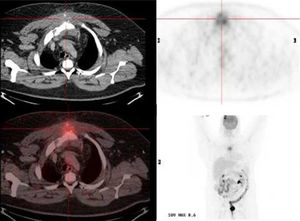

A 45-years-old male patient came to the Emergency Room due to a chest pain of a month of evolution, the physical examination was normal. The patient has a history of metabolic syndrome. Cardiac pathology was ruled out. A thoracic computed tomography (CT) scan was performed, where an destructive sternal bone lesion associated with a soft tissue mass located in the upper third of the breastbone was observed (approximate size 96mm×71mm×53mm) associated to a soft tissue mass located at the upper third of the breastbone were found, in addition to suggestive of malignancy bilateral axillary mediastinal adenopathy's (Fig. 1).

Thoracic computed tomography scan shows destructive sternal bone lesion associated with a soft tissue mass (approximate size 96mm×71mm×53mm) with a hypermetabolic lytic lesion at the manubrium-sternal junction, associated to a mass of perilesional soft. tissues, and infiltration of the upper mediastinal fat with a SUV max value of 8.6.

A PET-CT was performed, where a hypermetabolic lytic lesion at the manubrium-sternal junction, associated to a mass of soft tissue, with infiltration of the upper mediastinal fat with a SUVmax value of 8.6 were found (Fig. 1)